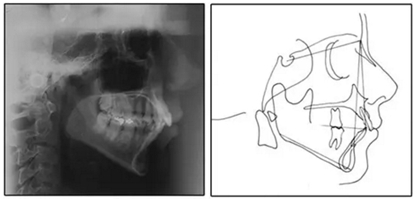

圖3. 治療前頭影側(cè)位片,頭影測量描跡圖和全口X光片

患者是一名39歲的白人婦女,病史不明。她主訴是她的右側(cè)顳下關(guān)節(jié)有不適癥狀,并希望改善她的笑容。她有一個對稱的臉型和一個II類2分類的微笑。她的側(cè)貌是凸的,90°的鼻唇角和骨性下頜骨發(fā)育不足??趦?nèi),上頜中線與面部重合,但下頜中線向右側(cè)偏移5mm;存在6mm的深覆蓋。她的兩側(cè)都是I類磨牙關(guān)系,左側(cè)是I類尖牙關(guān)系,右側(cè)是完全的II類尖牙關(guān)系。下頜右側(cè)第二前磨牙先天性缺失(圖1和圖2)。最初的全景片顯示了足夠的骨質(zhì)水平和全部的第三磨牙(圖3)。治療前的頭影測量片片和相應(yīng)的頭影測量圖(圖3)證實ANB為7°,Wits評估為6 mm的骨性II類錯合(表)。上頜切牙相對與面部和顱底的位置很好。下頜切牙前傾。診斷為II類2分類錯合畸形,伴有骨性下頜發(fā)育不足,右側(cè)顳下頜關(guān)節(jié)癥狀,下頜中線向右側(cè)偏移5mm,先天性右下第二前磨牙缺失。